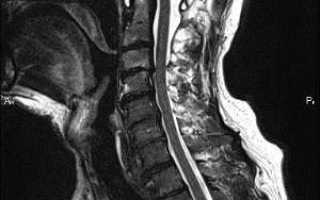

В современное время диагностировать заболевание не составляет особого труда, ведь симптоматика заболевания ярко выражена. Врач невролог при осмотре может установить диагноз, который потом при помощи МРТ или КТ будет подтвержден, или же опровергнут. С помощью МРТ можно определить размер грыжи, ее точное расположение, исключить любую другую патологию.